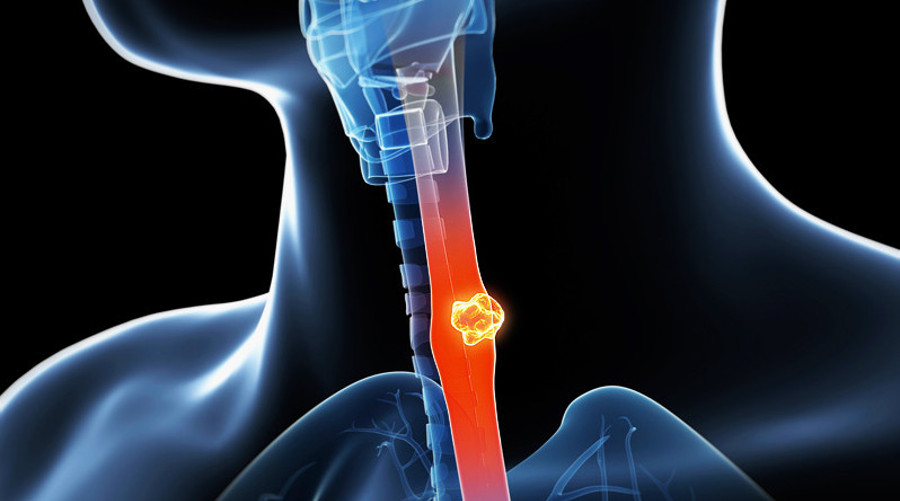

食管癌(或食道癌)指的是发生在食道的癌症,占2012年癌症死亡人数7%或者全部死亡人数的2%(2013年卫生部统计年鉴),占癌症死亡人数第5位。

食管癌的类型

- 鳞状细胞癌:多发病于食管的中上段,是食管内壁皮肤细胞的癌变。常见于发展中国家,包括我国,90%的食管癌属于此类,一般认为主要与吸烟和饮食习惯相关。

- 腺癌:多发病于食管的下段,是食管上皮组织中腺体细胞的癌变。常见于发达国家,吸烟,肥胖和胃反流是重要相关因素。